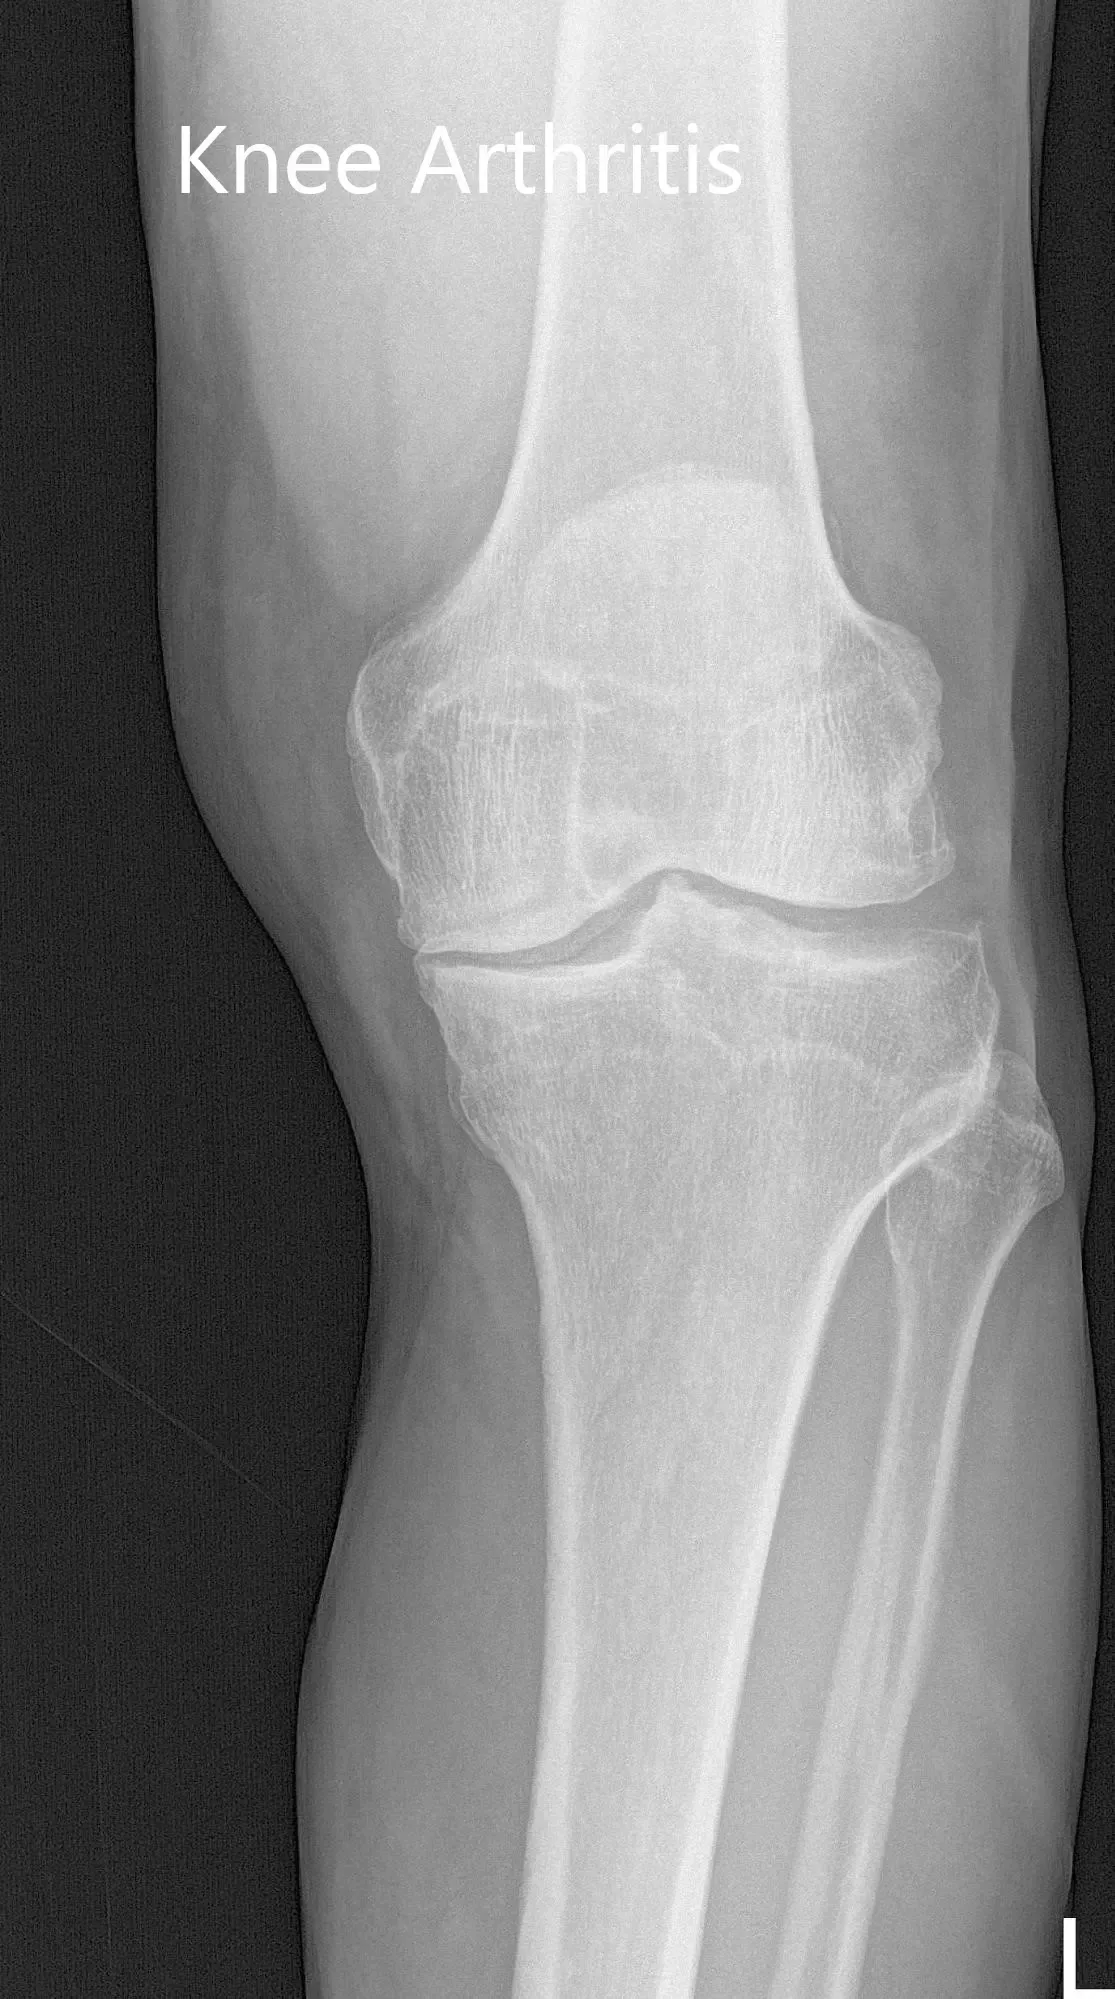

Her physical examination revealed mild knee swelling with a genu varus deformity. She had an antalgic gait with a decreased stance phase on the left side. There were no scar, sinuses or erythema on visible inspection. Palpation revealed medial joint line tenderness and medial patellar facet tenderness with copious joint crepitus on range of motion. End flexion was painful with no contracture. Imaging studies revealed tricompartmental osteoarthritic degenerative changes of the left knee.

Preoperative X-ray of the left knee showing AP and lateral views

Preoperative X-ray of the left knee showing AP and lateral views.